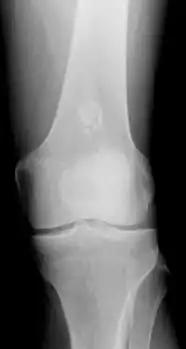

X-ray: Solitary enchondroma in long bone of thigh near knee

Diagnosistic tests include medical imaging.[2] Appearances on X-ray show a small lobe-shaped, dark tumor in the middle of the bone.[2] It typically contains white spots; calcified chondroid matrix (a "rings and arcs" pattern of calcification).[2] It does not extend into soft tissues.[6] Magnetic resonance imaging (MRI) and CT scan may be requested to further evaluate the tumor.[8]